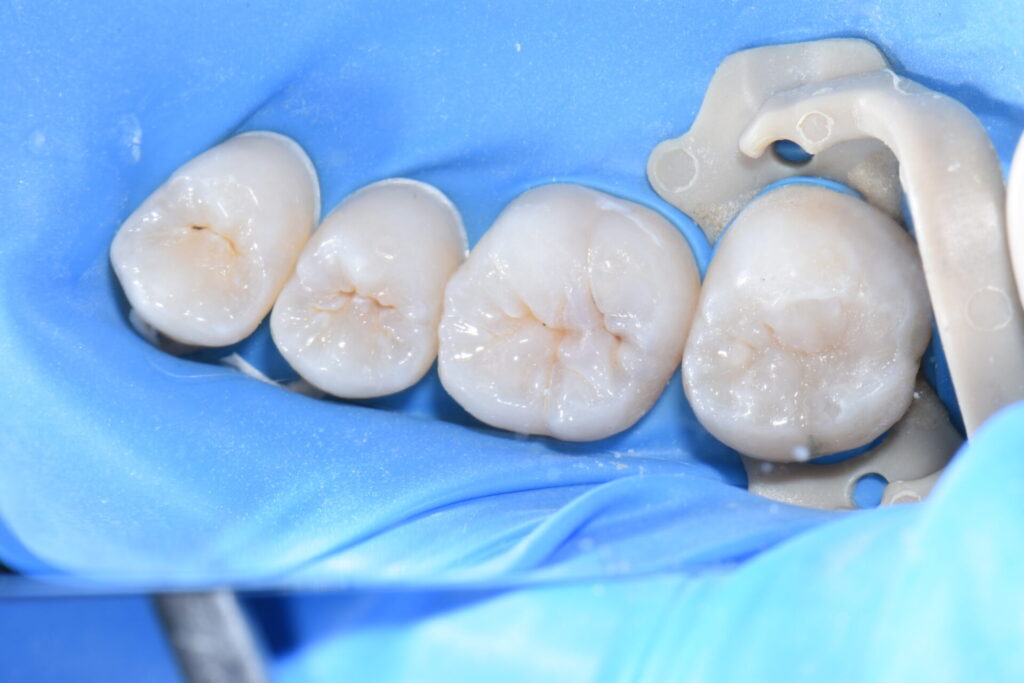

神経を取らずにMTAで歯髄を保護しダイレクトボンディング修復していきます。

術後 何日間か冷水痛・咬合痛を出ましたが経過は良好です。

最小限の治療介入で処置を終えることが出来ました。無自覚無症状で虫歯や歯周病は進行していきます。定期的な歯科健診と歯のクリーニングで口腔内を健康な状態に保つことは全身の健康のためにも重要です。